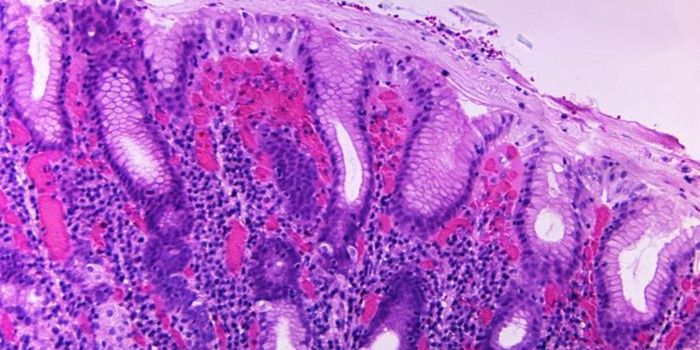

FEB 27, 2015Health & MedicineClostridium difficile (C. difficile, or C. diff) caused almost half a million infections among patients in the United St ...

FEB 27, 2015Health & MedicineATLANTA -- A nasty intestinal bug sickens nearly twice as many Americans each year as was previously thought, according ...

JUN 30, 2018ImmunologyA specific subset of immune cells could be targeted to better treat inflammatory bowel disease (IBD). A new University o ...

OCT 23, 2019ImmunologyDelivering gluten to the body in a friendly, harmless package may be the way for people with celiac disease to finally h ...